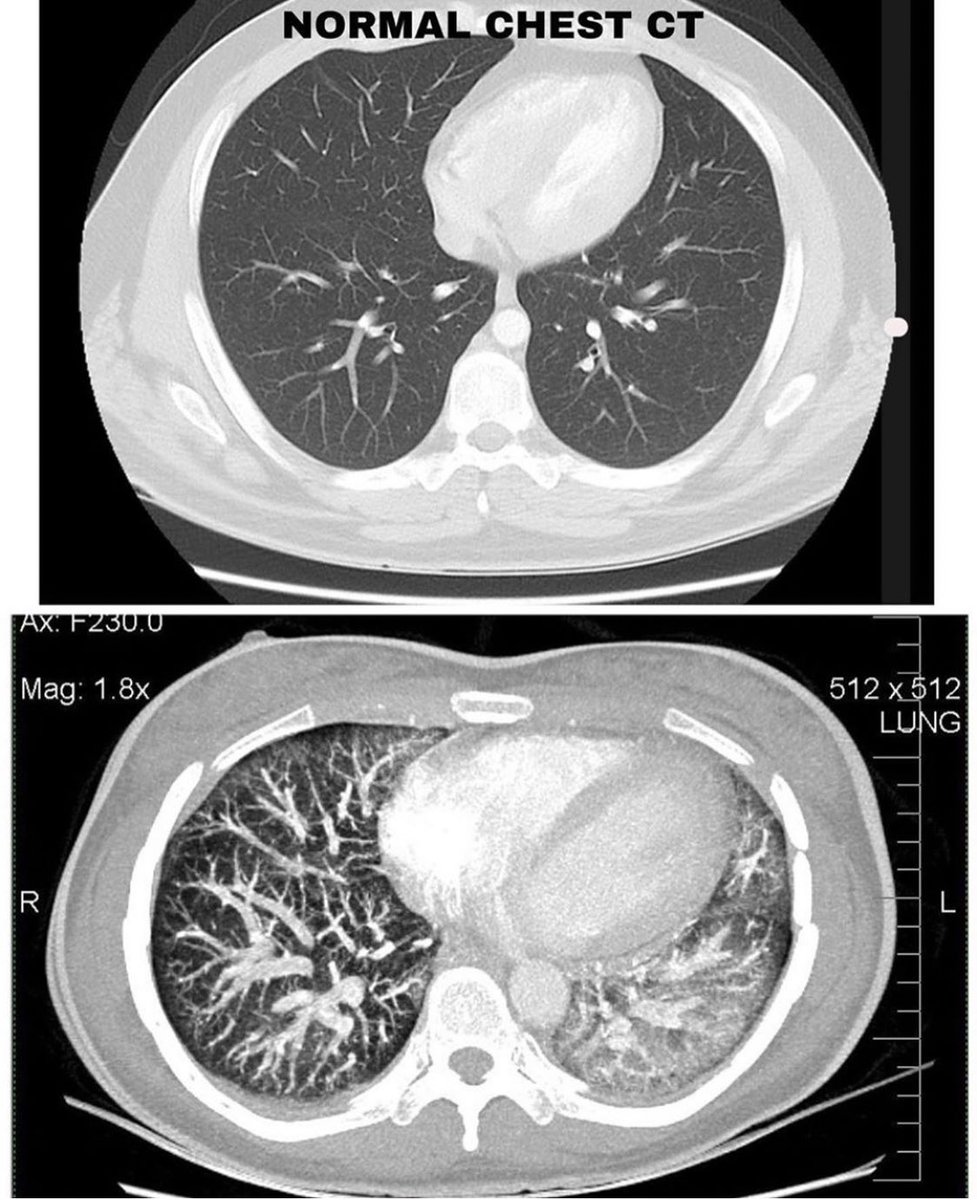

بينت الأشعة المقطعية تزايد في منطقة "الالتهاب" لتشمل الرئتين بالكامل، ولذلك تم تنويمها في العناية المركزة تحت العزل التنفسي والبدء في مضادات حيوية عن طريق الوريد